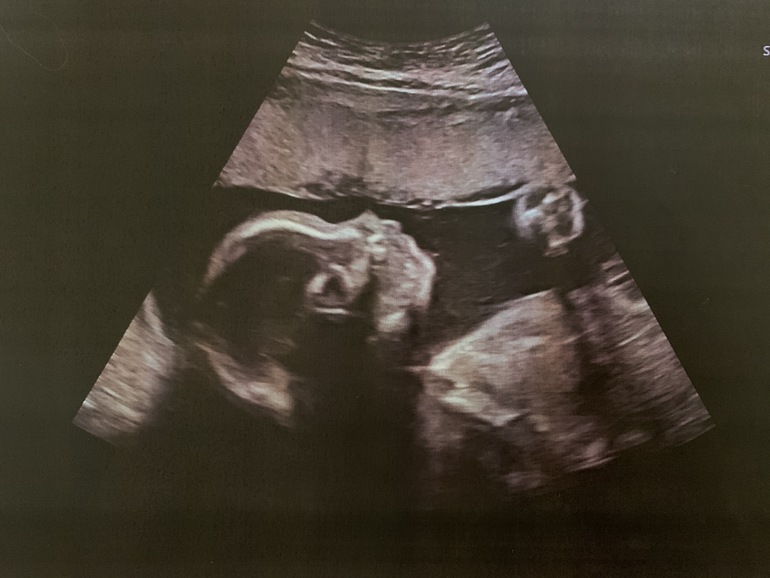

И немножко фото нашего малыша